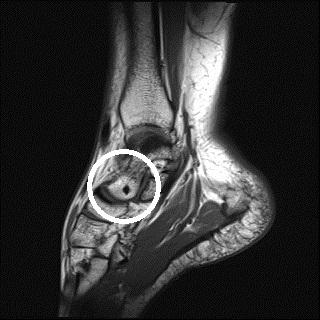

Mrt Aufnahme Vom Sprungelenk Schwarzer Fleck Im Knochen Was Kann Das Sein Sprunggelenk

Röntgenbild schwarzer fleck knochen. Ein Röntgenbild für einen Laien nicht sehr einfach zu interpretieren. Hilfe Röntgenbild schwarzer punkt knochen Ich denke als Laie kann man keine Röngenbilder beurteilenDieser Fleck ist möglicherweise ganz anders zu interpretieren als Sie das jetzt tunIch würde mir dazu keine Gedanken machenzumal Ihre Beschwerden ja auch an ganz anderer Stelle gelagert sindOb das ein Bildfehler ist wage ich zu. Dort lassen sich entsprechende Signalveränderungen feststellen - im abgebildeten MRT zeigen sich im schwarzen Knochen weiße Flecken als Zeichen einer Flüssigkeitseinlagerung.

Röntgenbilder und Ultraschall können ein Knochenmarködem BME bone marrow edema nicht darstellen. Wir hoffen wir konnten Ihnen weiterhelfen - Ihr Lifeline Gesundheitsteam. Weiche Gewebe wie Fett und Muskeln lassen fast die ganze Strahlung durch sie sehen im Röntgenbild schwarz aus.

Ein Röntgenbild für einen Laien nicht sehr einfach zu interpretieren. Mein Orthopäde konnte sich auch nicht wirklich erklären was das ist. Diese steigt nach oben und ist dann unterhalb der linken Zwerchfellkuppel als sehr röntgendurchlässig zu sehen. Dort lassen sich entsprechende Signalveränderungen feststellen - im abgebildeten MRT zeigen sich im schwarzen Knochen weiße Flecken als Zeichen einer Flüssigkeitseinlagerung. Eine dunkle Stelle auf der Aufnahme sagt zunächst nur aus dass der Knochen hier die Röntgenstrahlen leichter hindurch lässt also das Gewebe nicht so dicht ist. Die Diagnose erfolgt durch eine Kernspintomographie MRT. Auf dem Röntgenbild sind weiße Flecken oben rechts im rundlichen Knochen denke Mal dass das das Ende des Oberarms ist zu sehen.